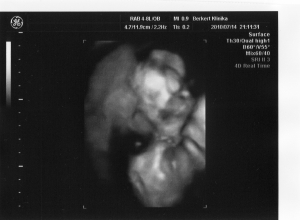

Vivi! kis zsarnok